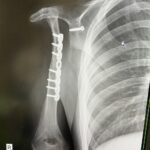

@miyabi_udenashiさん(@miyabi_udenashiさんより提供)